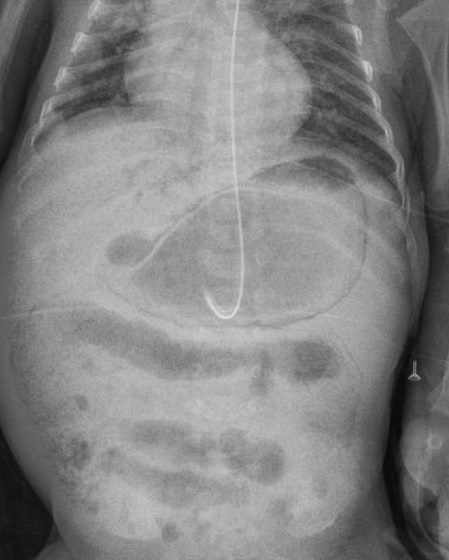

On day 128, he was noted to have abdominal distension, apnea, and non-bilious vomiting. C-reactive protein (CRP) was slightly raised but his abdominal X-ray showed gastric pneumatosis and dilated intestinal loops (Fig. 1). Septic work including blood and urine culture were sent and antibiotics commenced, supplemental nasal O2 was started. At the time of developing gastric pneumatosis the baby was on low birth weight formula feeds via nasogastric tube.

Figure 1

X-ray abdomen showing gastric pneumatosis.